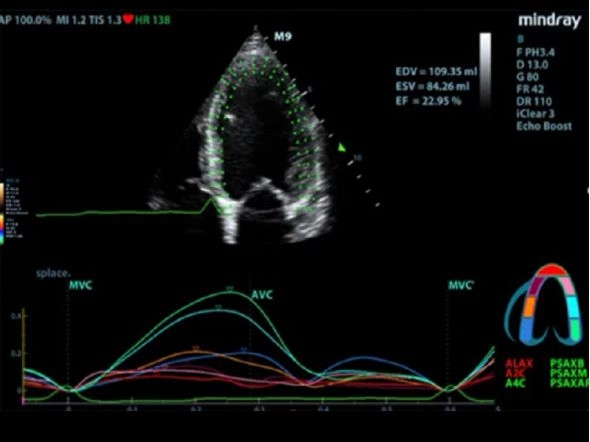

Оценка движения миокарда методом спекл-трекинга и количественный анализ ZST+

- Отличное качество изображения в B-режиме для точного диагноза

- Поддержка анализа в онлайн-режиме и режиме постобработки

Исследование сердца взрослого анатомический M-режим